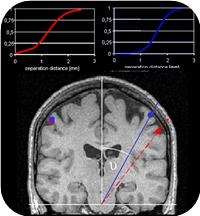

Plasticity / Learning: Tactile PlasticityHow are neural structures subserving tactile processing reorganized through learning or injury? How do neural changes affect tactile perception? Which rules govern the improvement of tacile and haptic skills?  Learning-induced plasticity - Perceptual learning, role of motivation and attention

- Relation between changed perception <–> reorganisation